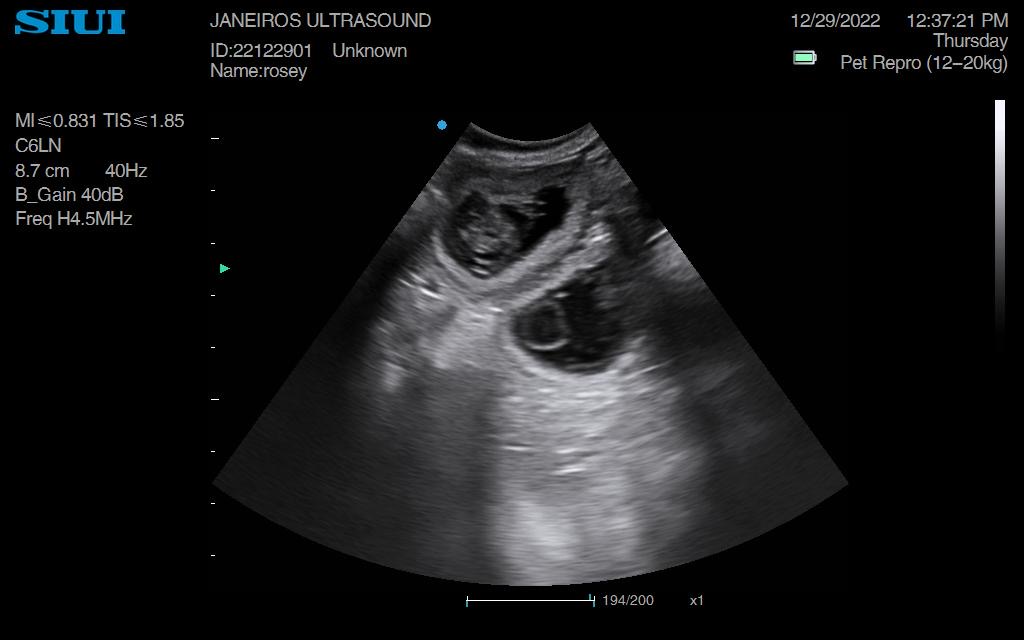

Rosey Dachshund Ultrasound Conisbrough Animal Ultrasound Association Dachshund Ultrasound The best way to determine if your dachshund is pregnant is with a blood test performed at the veterinarian. The vet should be able to determine the number of puppies your dachshund will have, as well as any potential abnormalities. The pups continue to grow during this stage. Take your dachshund to the vet for a blood test or ultrasound. Dachshund Ultrasound.

From www.animalultrasoundassociation.org

Rosey Dachshund Ultrasound Conisbrough Animal Ultrasound Association Dachshund Ultrasound Take your dachshund to the vet for a blood test or ultrasound if you suspect she is pregnant. During week 4, visit the vet once more to confirm the pregnancy through ultrasound examination. The spine and the eyes start to develop, and their faces begin to shape up. The best way to determine if your dachshund is pregnant is with. Dachshund Ultrasound.

Rosey Dachshund Ultrasound Conisbrough Animal Ultrasound Association Dachshund Ultrasound Around two to three weeks after. Your vet can perform an ultrasound to confirm the pregnancy and check the health of the embryos. At this stage, the fetuses are about the size of a. You might notice that your dog’s nipples are slightly enlarged. Ultrasound of a dachshund at approximately 33 days gestation. During week 4, visit the vet once. Dachshund Ultrasound.